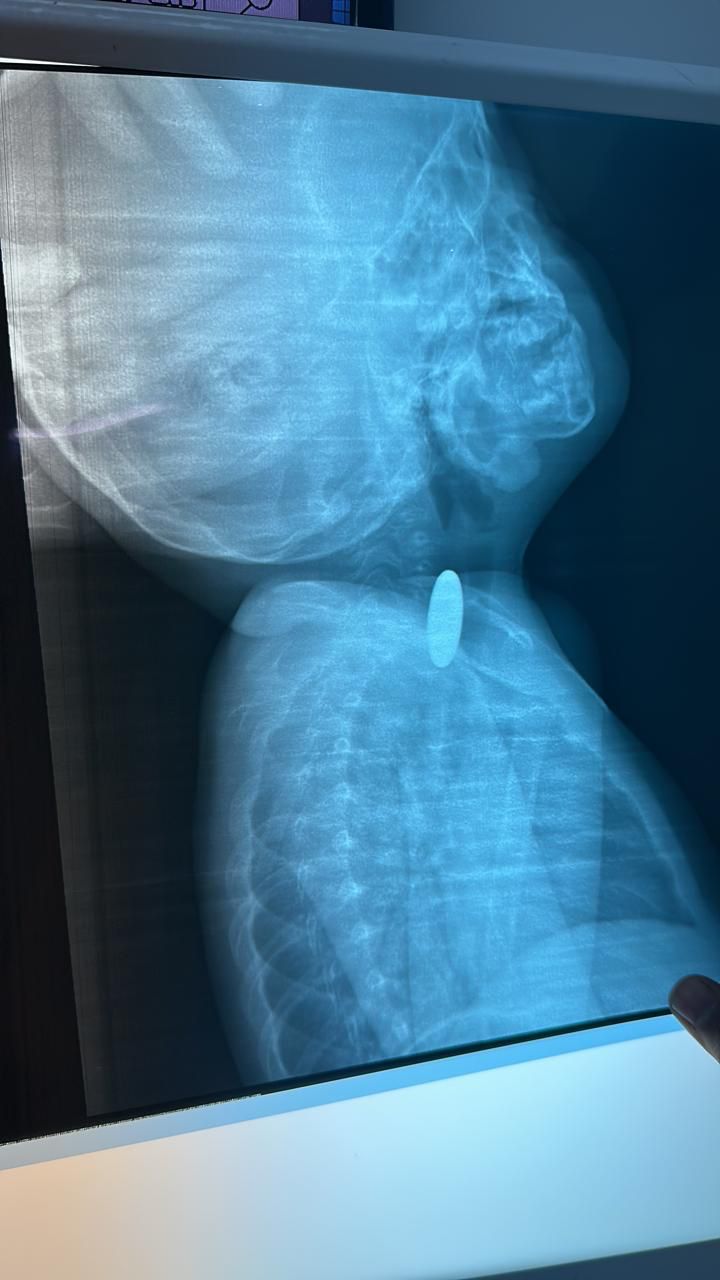

تمكن – بفضل الله – فريق طبي بمستشفى رابغ العام من استخراج قطعة معدنية من بلعوم طفل يبلغ من العمر عامان خلال عملية لم تستغرق أكثر من 10 دقائق.

وأوضحت (صحة جدة) أن الطفل قَدِم إلى طوارئ المستشفى وهو يشكو ابتلاع جسم غريب (قطعة نقود معدنية) كانت قد علقت في منطقة البلعوم؛ مما تسبب في اختناق وعدم قدرة على البلع؛ حيث قرر الطاقم الطبي إجراء عملية عاجلة بالمنظار لإزالة الجسم الغريب، والتي تبين أنها قطعة معدنية نقدية، وقد كُللت العملية بالنجاح دون حدوث مضاعفات – ولله الحمد – وقد غادر الطفل المستشفى وهو بصحة جيدة.